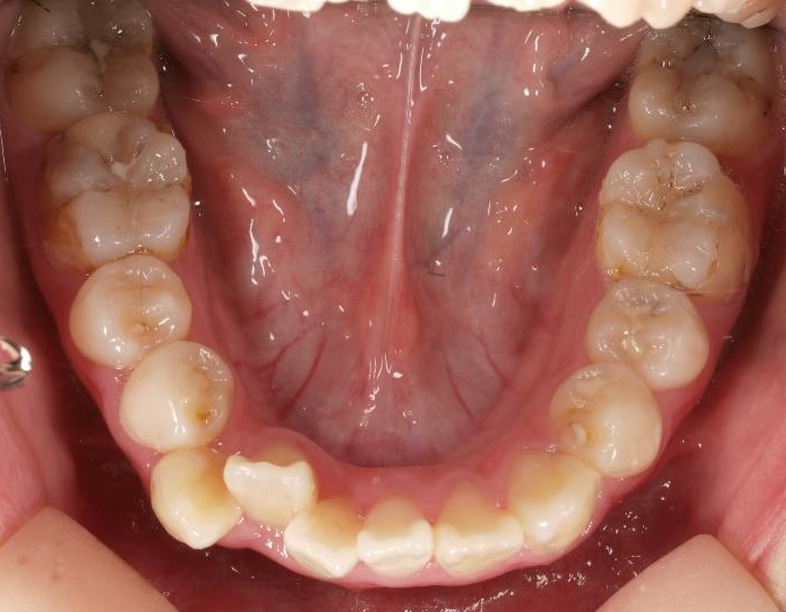

乱ぐい歯、でこぼこがとても酷い状態になります。歯が前後的に重なってしまっている、八重歯になっているなどがこのジャンルに入ります。

顎の大きさと歯の大きさのギャップが大きく、時には歯を抜かないと矯正治療ができない場合もあります。当院では治療期間が長くなるが抜かない治療方針など、一つの治療プランだけでなく、さまざまな可能性の治療方針を説明させて頂くよう心掛けております。こういった考え方はインフォームド・チョイスと言われ近年大切にされている考え方と言われております。

治療前

治療終了前